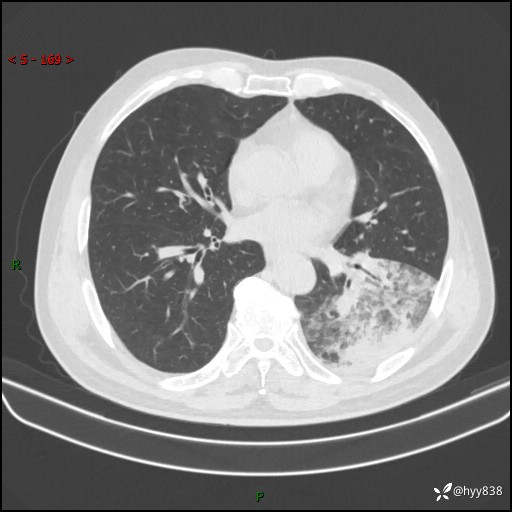

59岁/男,发热伴咳嗽3天。白班偶遇,“大叶性肺炎”,病原体挑战---结果公布~

【患者信息】:59岁/男

【主诉】:发热伴咳嗽3天

【检查】:胸部CT平扫